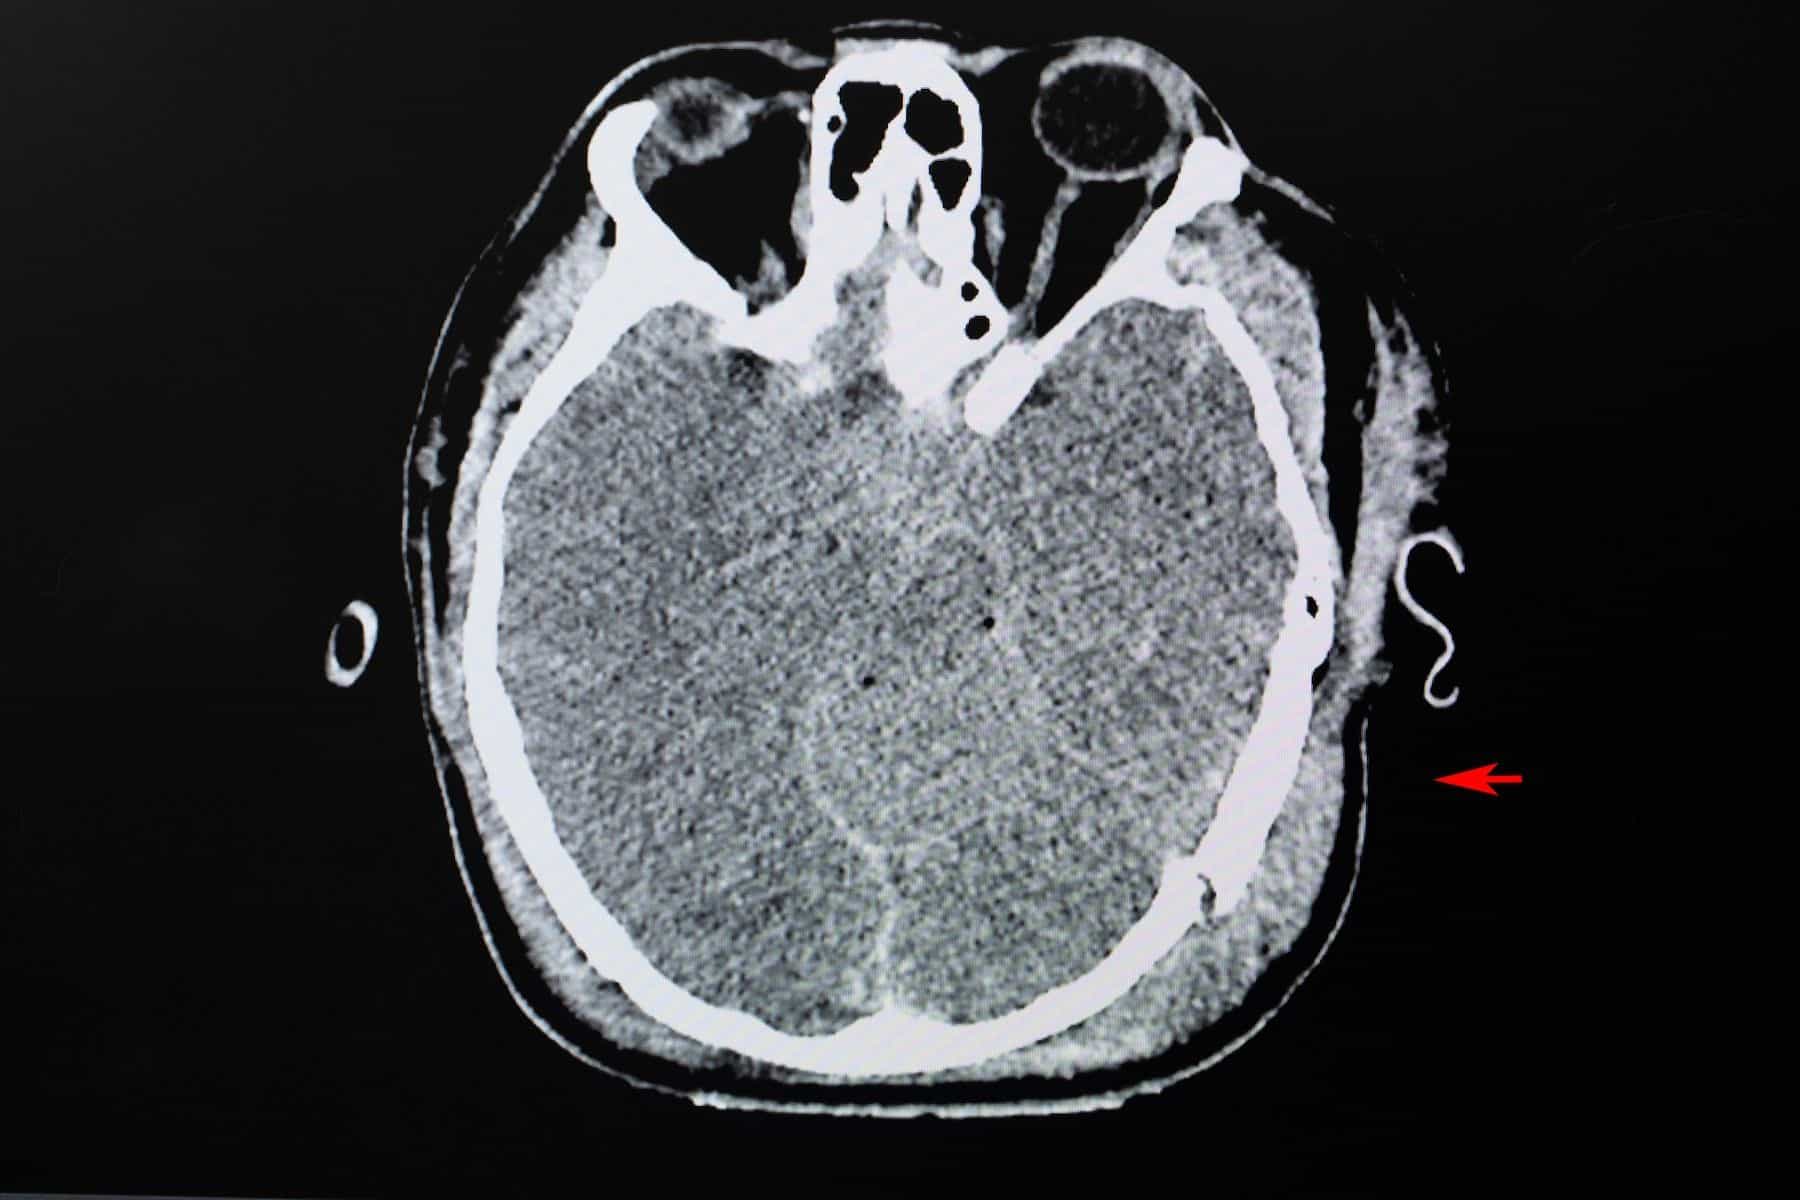

Different testing modalities, including the Glasgow Coma Scale (GCS) score, imaging, and clinical biomarkers, have been used to help diagnose moderate and severe TBIs. Computed tomography (CT) or magnetic resonance imaging (MRI) are the mainstays for assessing soft tissue damage to the brain such as:3

Skull fractures resulting from TBIs are generally assessed using CT scans of the head and include:3